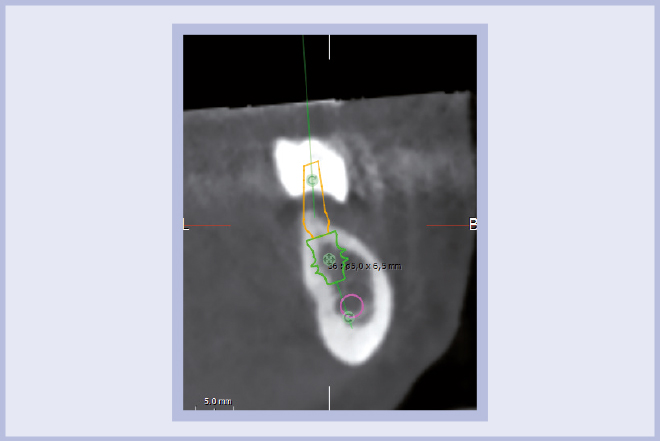

Per riabilitare la masticazione del terzo quadrante, con osso gravemente atrofico, si procede allo studio del caso con esame radiologico 3D e posizionamento virtuale di impianti Exacone® Leone. La prima valutazione è stata eseguita con il software dell’apparecchio radiografico Cone Beam presente in studio. Dopo aver verificato che la quantità di osso residuo fosse sufficiente all’inserimento di due impianti, seppur di dimensioni ridotte, in sede 3.5 e 3.6 senza l’ausilio di tecniche di rigenerazione ossea (Figg. 1-3), si richiede al laboratorio di confezionare una mascherina radiologica con ceratura diagnostica radiopaca e repere standardizzato a livello incisale come da protocollo Leone (Figg. 4, 5). Si verifica quindi clinicamente l’assenza di mobilità della mascherina dopo il posizionamento nel cavo orale del paziente (Figg. 6, 7). Si effettua una CBCT con la mascherina in posizione e l’esame viene inviato in formato DICOM all’azienda Leone assieme al modello master della paziente. L’azienda provvede quindi ad inviare agli Autori il software 3Diagnosys (software di progettazione) in licenza monopaziente con caricati i file DICOM ricevuti; il software viene quindi utilizzato per la progettazione definitiva del caso (Figg. 8-12).

- Figg. 8-12 – Pianificazione implantare con software 3Diagnosys Leone

- Fig. 11

- Fig. 12